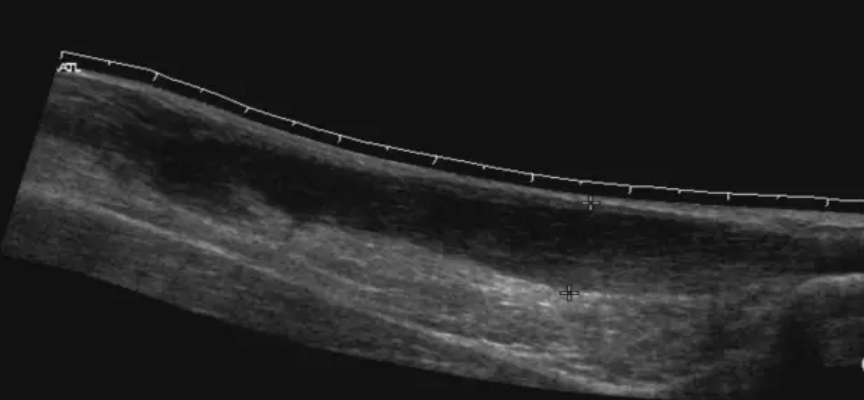

A

Tendón de Aquiles normal